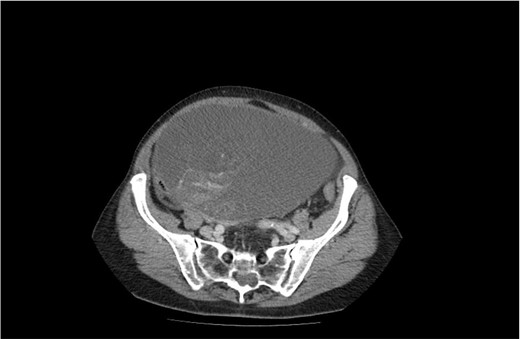

A 75-year-old woman with a complaint of heaviness in the abdomen with gradually increasing dimensions, as well as heaviness in the groin areas with pronounced constipation for several years, was consulted by a surgeon. Abdominal ultrasound revealed a large cystic formation with a hypoechoic appearance with isoechoic components in it with size of ~198 mm/d, compressing adjacent distended intestinal loops. To the left of it, a smaller structured cystic zone ~5 cm/d was visualized. Subsequent computed tomography (CT) of the abdomen and pelvis with contrast revealed a well-demarcated large cystic mass on the right of the pelvis, tracing cranially preaortic, retroperitoneally and reaching the level of the epigastrium, measuring 150/210/138 mm/d, thin-walled with homogenous contents and an adherent appendix to the wall. Numerous thin septa were visualized inside (Fig. 1). A second finding with a cystic structure is present on the left of the small pelvis with a size of 69/85/100 mm/d in contact with the main formation along the lower lateral and a contour of 7 cm/d. There is a herniation of the right lateral surface of the bladder into the right inguinal canal, a transitional herniation of the sigmoid to the left inguinal canal. Computed tomography confirm an ovarian cystadenoma on the right. Laboratory indicators did not give a deviation. A joint decision was made with a gynecologist to perform a laparotomy with hysterectomy (Fig. 2), bilateral adnexectomy, and appendectomy. Intraoperatively, the finding was consistent with that described by CT. The histology result revealed a serous ovarian cystadenoma on the left and fallopian tube with an abudance of cystically transformed Walthard’cell nests. The same changes were also described in the right fallopian tube, mucinous ovarian tumor with borderline malignancy, and appendix fibrinous purulent periappendicitis. The patient had no postoperative complications and was discharges on the seventh postoperative day.

CT image of a large ovarian mucinous cystadenoma of the left ovary.